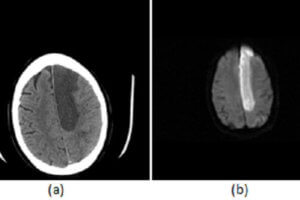

Acute Infarct on CT

The recent use of intravenous tissue plasminogen activator (TPA) to treat acute stoke has resulted in the introduction of “code strokes” in many emergency rooms, which typically require the coordinated efforts of... Read more »